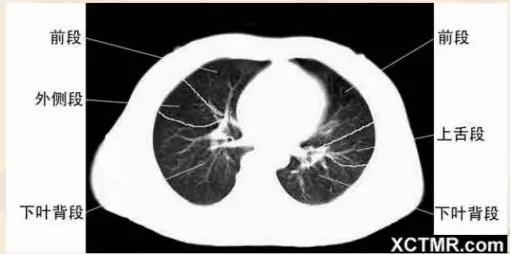

左主支气管层面

右中叶支气管层面